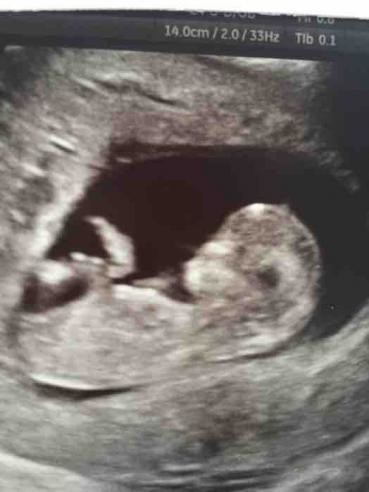

12-week scan . If you're pregnant in England you'll be offered an ultrasound scan at around 10 to 14 weeks of pregnancy . This is called the dating scan . It's used to see how far along in your pregnancy you are and check your baby's development . The scan may also be part of a screening test for Down's syndrome .

Ultrasound in early pregnancy (before 12 weeks) - Dating Scan Dating ultrasound A 'dating ultrasound' or 'dating scan' is a scan done early in pregnancy (before 12 weeks) . It is usually done to check how many weeks pregnant you are and therefore to calculate the estimated due date, but it can be done for other reasons . Only a few women need a dating scan .

A dating scan might be recommended before 12 weeks to confirm your due date if you are unsure of your last menstrual period or your date of conception . The scan is optional and not everyone will have it . You can discuss whether you want or need a dating scan with your doctor or midwife . A dating scan is usually done to check how many weeks' pregnant you are, but can be done for other reasons, such as if you have had bleeding during your pregnancy or you have had previous miscarriages .

The dating scan is usually done at some point between 8 weeks and 14 weeks pregnant .NICE recommends it's done between 10 weeks and 13 weeks . You will have had earlier appointments and may have had an early scan if you've had any concerns such as bleeding, but otherwise this is the first time you'll get to see your baby, so it's a real milestone in your pregnancy .

When will I have my dating scan ? You'll have a dating scan appointment, also known as a 12-week scan , between about 10 weeks and 14 weeks of pregnancy . This is usually the first scan you'll have, so it's likely to be a significant moment for you . You'll only have a scan before 10 weeks in certain situations . For example, if you had assisted conception, an early scan will check the embryo is developing as it should .

When will I have my dating scan ? The dating scan is an ultrasound that can be done from seven weeks of pregnancy but they usually happen a little later . It's the best way to predict your due date (Butt and Lim 2014, PHE 2014, SOGC 2019, Van den Hof et al 2019) . It's also a chance for you to see your baby for the first time . Not all moms-to-be have a dating scan .

When is the Pregnancy Dating Scan Recommended? The first dating scan is usually done after 10 weeks, and this is the norm all over the world . This doesn't mean that you cant do a dating scan at 8 weeks either . There are many moms who have done the same and have had accurate results .